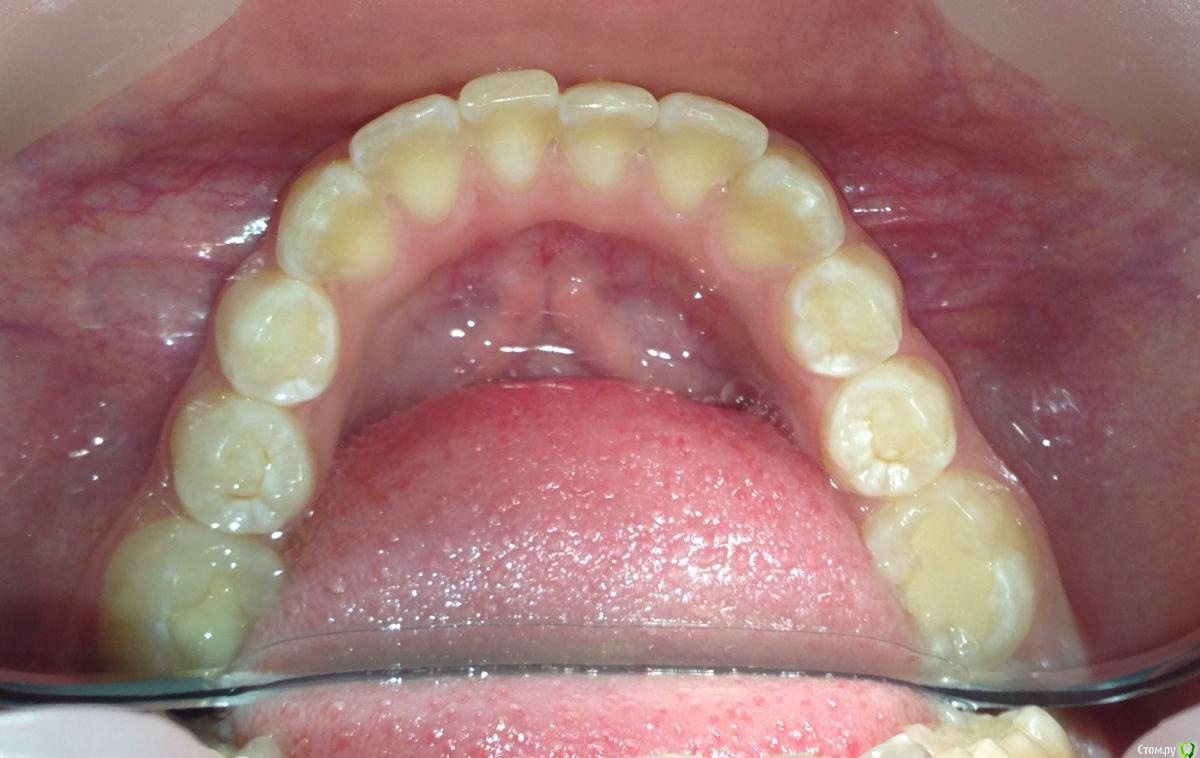

Пациентка 14 лет. Было принято решение лечить без удаления, тк. профиль не позволяет да и ретропозиция нч. Лечение идет. Я назначила ранние эластики слабые, на 17/25 нити на вч и 18 нити на нч. по 2 классу короткие 3,4-4,5. Пациентка пришла через месяц жалуется на щелканье челюсти во время ношения эластиков и сразу после их снятия. Т.е. если открывает рот, то челюсть скачкообразно двигается и щелчками. Последние 2 недели, когда много говорит, то вообще стала заедать. Это она так сказала. После отмены эластиков (страшно), через неделю пришла, рот открывает ровно, без девиации, щелчков нет. Вопрос: почему щелкает и что с этим делать? По поводу прикуса, посоветуйте, пожалуйста, как нормализовать? Аппарат типа гербста? может ей твинблок сделать? Эластики? К сожалению другими методами я пока что не владею. Спасибо, очень жду ваших советов.